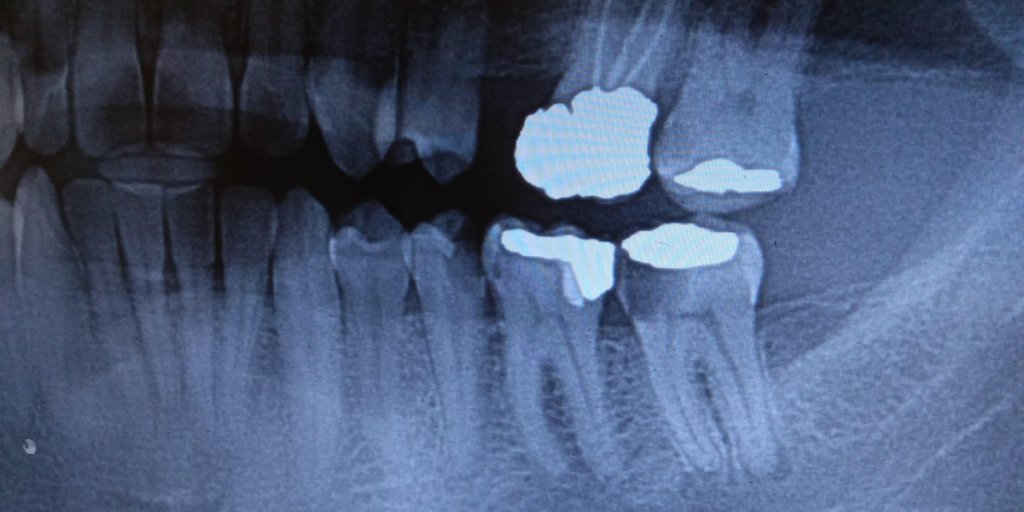

These cavities are often found during dental exams and X-rays, before you feel pain. If you get cavities despite good oral hygiene, hidden decay between teeth is worth checking.

A decay risk assessment considers your cavity history, dietary habits, signs of dry mouth, tooth shape, and enamel strength. It also looks for grinding, gum recession, and the edges of fillings or crowns. If you are doing orthodontic treatment in Clifton, it also checks how cleaning access has changed. This helps a dentist identify the causes of your frequent cavities and choose the right preventive tools for you.

Why Dental Exams Matter Even With Excellent Oral Hygiene

Early cavities often do not hurt. Regular dental exams and visits help catch small problems early. Cleanings remove tartar that brushing can’t remove. We can also help fix oral hygiene issues before they lead to bigger problems. If you’ve had cavities despite good oral hygiene, routine monitoring can prevent surprises.